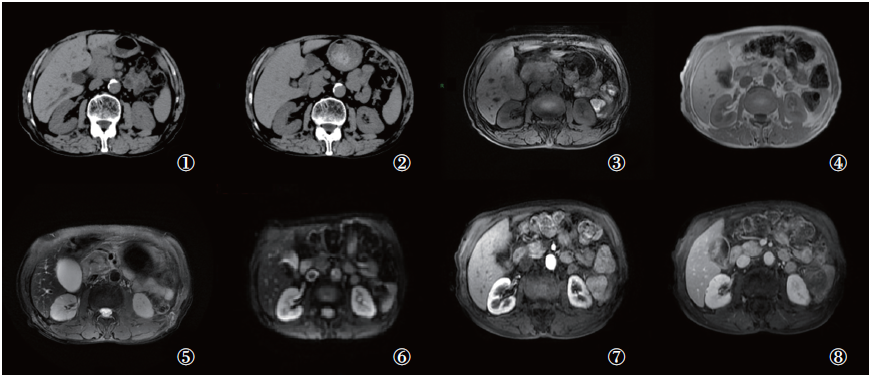

患者口服糖皮质激素治疗4周后行CT平扫及MRI增强检查显示病灶明显缩小(图3), 血清IgG4检测值为1.2 g/L(参考值80~1 400 mg/L), 同时患者上腹部疼痛症状完全消失。

图3 治疗前与治疗4周后CT平扫和及MRI对比

注: ①治疗前CT平扫; ②治疗4周后CT平扫; ③治疗前T1WI; ④治疗4周后T1WI; ⑤治疗前T2WI; ⑥治疗4周后T2WI; 可见治疗4周后病灶范围明显缩小, T1WI信号较治疗前稍升高, T2WI信号较治疗前稍减低; ⑦~⑧治疗4周后MRI增强显示病灶呈充填式强化改变

Fig.3 Contrasted CT scan and MRI before treatment and 4 weeks after treatment

Note: ① Before treatment CT scan; ② CT plain scan of after 4 weeks of treatment; ③ Contrasted T1WI; ④ MRI TIWI of after 4 weeks of treatment; ⑤ Before treatment MRI T2WI; ⑥ MRI T2WI of after4weeksoftreatment; it showed that the lesion area was significantly reduced after 4 weeks of treatment, the signal on T1WI was slightly higher than before treatment, and the signal on T2WI was slightly lower than before treatment; ⑦~⑧ MRI enhancement after 4 weeks of treatment showed that the lesion showed filling-enhancing changes